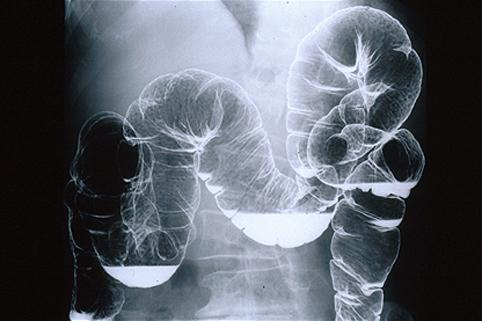

식도를 포함한 MLP(multiple Lymphomatous Polyposis)형의 소화관병변을 나타낸 악성림프종

[Image-ID:6820]

악성 림프계종양/MLP형 악성 림프종

대장/2구역 이상의 대장에 걸치는 것

X-P

1~9

유(동시성 및 이시성)